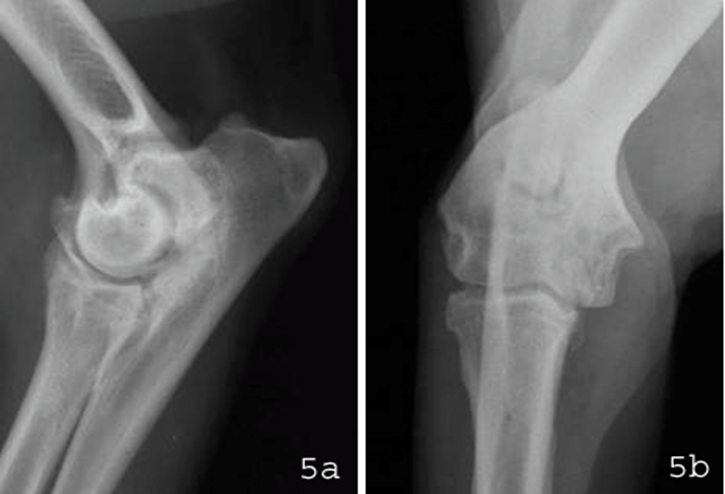

Die direkte Diagnose ist nur dann zu stellen, wenn der FPC deutlich verlagert ist. Ansonsten basiert die Verdachtsdiagnose eines FPC auf dem Vorliegen von anderen röntgenologischen Veränderungen, wie beispielsweise Stufenbildung, sekundäre Verdichtungen in der Knochenstruktur oder den im weiteren Verlauf der Erkrankung entstehenden Arthrosen. Diese sind etwa ab einem Alter von sieben bis neun Monaten röntgenologisch zunächst nur dezent zu erkennen und treten ab dem 12. Lebensmonat an verschiedenen Lokalisationen im Gelenk meistens deutlicher in Erscheinung (Abb.5).

Abbildung 5: Röntgenbilder vom rechten Ellbogengelenk eines 4-jährigen Deutsch Drahthaar-Rüden mit FPC. Auf den Röntgenaufnahmen in seitlichem Strahlengang (a) und von vorne (b) sind deutliche Arthrosen an verschiedenen Lokalisationen erkennbar.